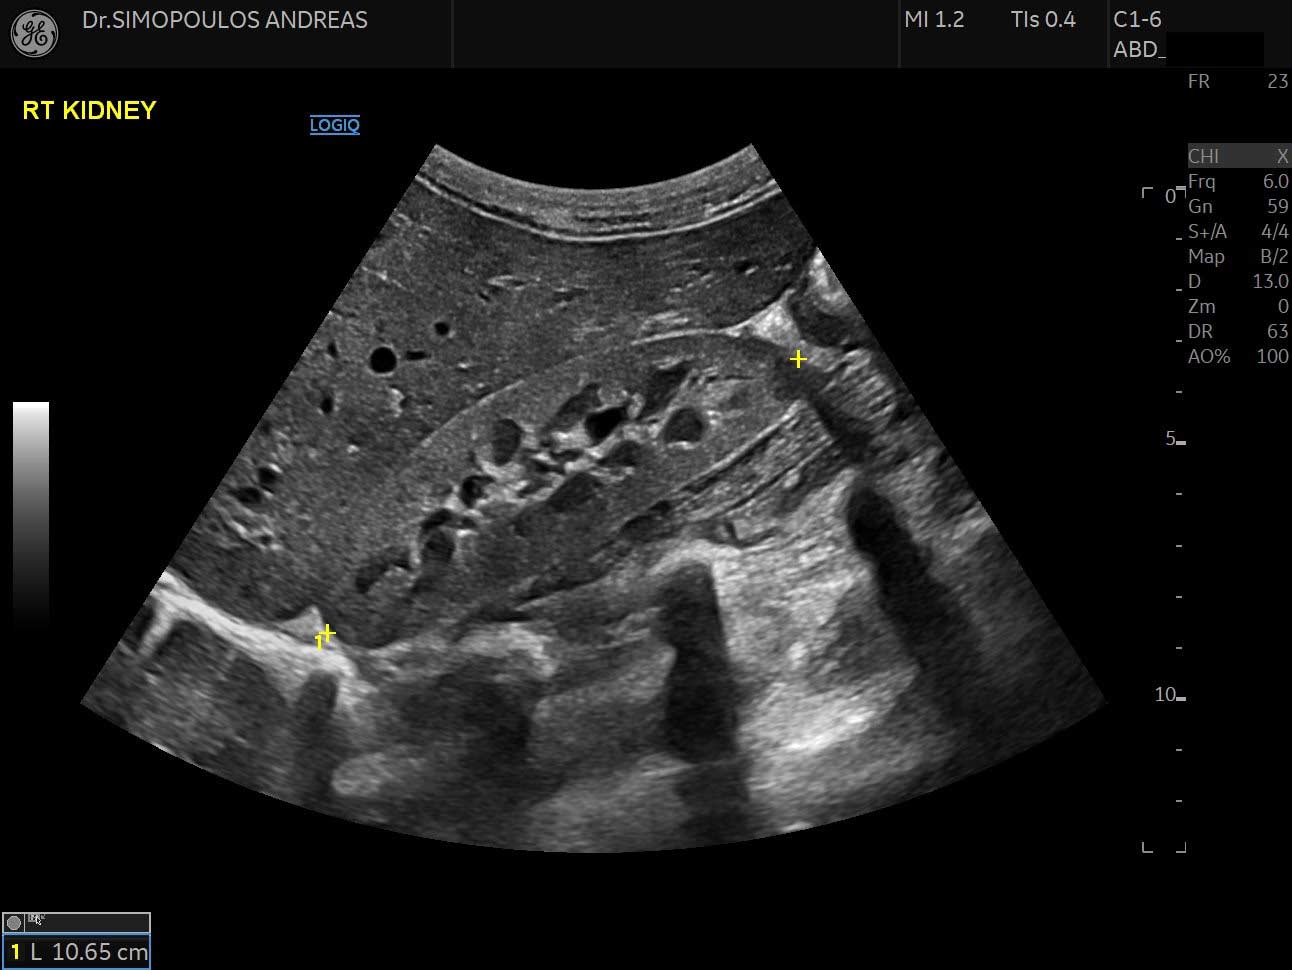

- Ουροποιητικού συστήματος: νεφρών – ουρητήρων - ουροδόχου κύστεως